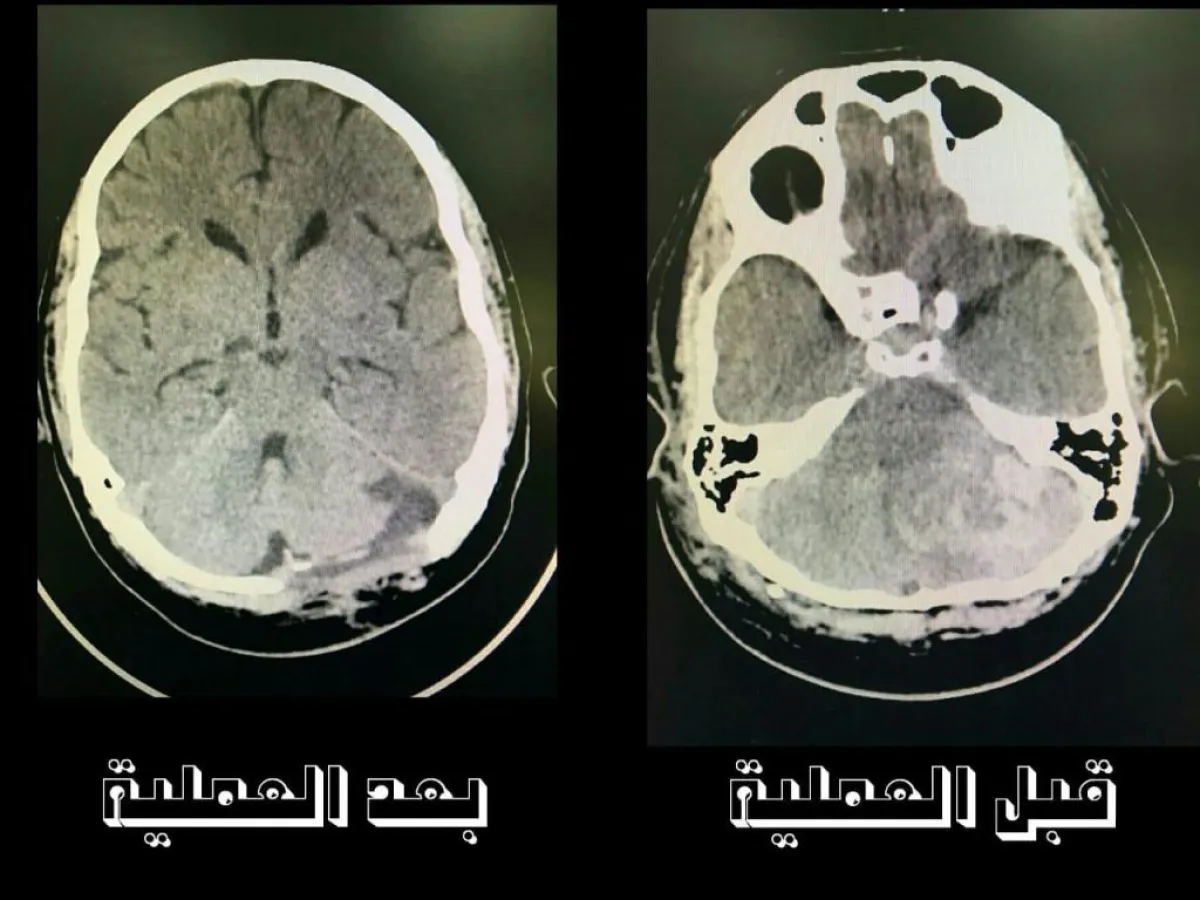

أوضح الدكتور وليد القذافي إستشاري جراحة المخ والأعصاب أنه تم استقبال حالة المريض بقسم الطوارئ وهو يعاني من نقص شديد في الوعي كشبة غيبوبة، وأجريت له كافة الفحوصات الطبية منها الإشعاعية التي بينت وجود ورم دموي كبير الحجم ونزيف حاد بالمخيخ مما أدى إلى الضغط على مراكز التنفس ونبضات القلب في المخ كادت أن تؤدي بحياته للوفاة.

و تم نقل المريض وبشكل عاجل إلى غرفة العلميات وأجريت له عملية جراحية دقيقة من نوعها، تم خلالها إزالة الورم الدموي كلياً بكل دقه ونجاح دون حدوث أي مضاعفات أثناء العملية الجراحية، شارك في إجرائها الدكتور محمد الشاطر أخصائي جراحة المخ والأعصاب وبتواجد أستشارية التخدير الدكتورة إيمان وكذلك طبيب التخدير الدكتور أنس الجارحي، وبعد الإنتهاء من العملية الجراحية للمريض تم نقله إلى العناية المركزة لوضعة تحت الملاحظة الطبية المركزة وعند التأكد من استقرار الحالة الصحية للمريض نقل إلى أجنحة التنويم الخاصة بجراحة المخ والأعصاب لستستقر صحته.